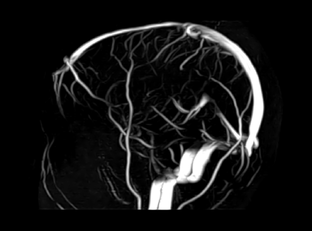

МРТ, КТ или УЗИ сосудов?

Зачастую, при назначении исследований сосудов различными методами, Вы можете задаваться вопросами: В чем отличие этих методов: КТ, МРТ и УЗИ сосудов? Зачем делать несколько исследований, а не сделать одно? Что является наиболее безопасным и оптимальным для меня? На эти вопросы мы в первую очередь постараемся ответить, попутно раскрываю суть и цели назначения каждого исследования. Разберем на примере исследований сосудов головного мозга, так как данная область является наиболее значимой и востребованной на настоящее время, и может быть исследована вышеизложенными методиками...